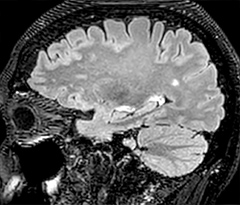

The abbreviated MS protocol for brain is only around 9 minutes, so in case of suspected multiple sclerosis, one or two more advanced sequences may be added, such as PSIR (phase sensitive inversion recovery) or susceptibility-weighted sequences to help us make more confident diagnoses in these inflammatory cases.

In this example, the optional 3D multishot susceptibility weighted sequence with 0.6 mm isotropic voxels is 2 lesions with a central vein sign (arrows) and one lesion with a phase-rim sign (arrowhead). The total scan time, including SmartBrain and axial PD/T2 3mm, is 11:10 min. and is 18:30 min. with the optional 3D PSIR and 3D SWI multishot included.

“We used to have long examination times for certain types of patients, a few lasting more than 40 minutes,” says Dr. Savatovsky. “What is remarkable, is that now all these examinations are below 30 minutes, which opens up opportunity to add more sequences when needed. It’s really hard to keep a patient for more than 40 minutes in the scanner, but because we have now cut scan times by at least 10 minutes, we can add more sequences without making the exam too long. And this is where the new system helps us make a difference. Examples include our examinations for informing brain tumor classification or giant cell arteritis workup, or for intracranial wall imaging – so in patients where we need several advanced sequences or high resolution sequences.” “We added three additional sequences in our brain neoplasm classification exam: a 3D SWI sequence, APT and ASL on top of 3D morphologic sequences, an isotropic DSC (dynamic susceptibility contrast) and multivoxel spectroscopy. I think that in patients that need a classification for brain mass, for example, we can provide a more detailed and confident diagnosis than before, allowing the clinicians to decide for either a medical workup if no tumor is suspected, or for neurosurgery as soon as possible if a neoplasm is suspected.” “In multiple sclerosis patients, we increasingly include a multishot susceptibility sequence [3] in our routine cases, thanks to the shorter scan times. Our abbreviated MS protocol for brain is around 8 to 9 minutes, so we can ask for one or two additional sequences to visualize the central veins, or to get an additional contrast to better depict posterior fossa lesions. In cases of white matter lesions of unknown significance on FLAIR images, for example when we see high signal hyperintensities in the brain, we can add on more advanced sequences such as PSIR (phase sensitive inversion recovery) or susceptibility-weighted sequences to help us in distinguishing between MS and nonspecific or vascular abnormalities in these inflammatory cases.”